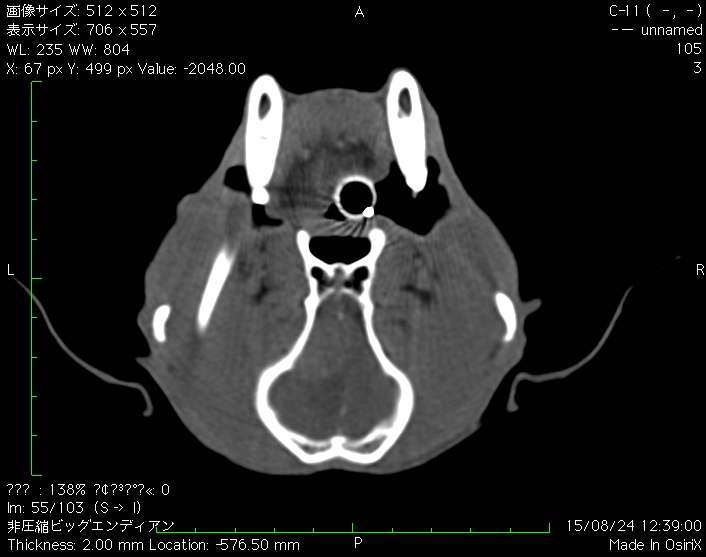

犬の脳腫瘍(髄膜腫)について

髄膜腫は脳の外側、頭蓋骨の裏側にある硬膜という膜から発生する腫瘍。つまり脳そのものから生じる腫瘍ではなく、脳の外側から発生して脳を外側から圧迫する。